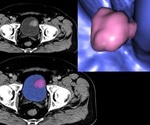

Machine learning model accurately classifies the stages of bladder cancer